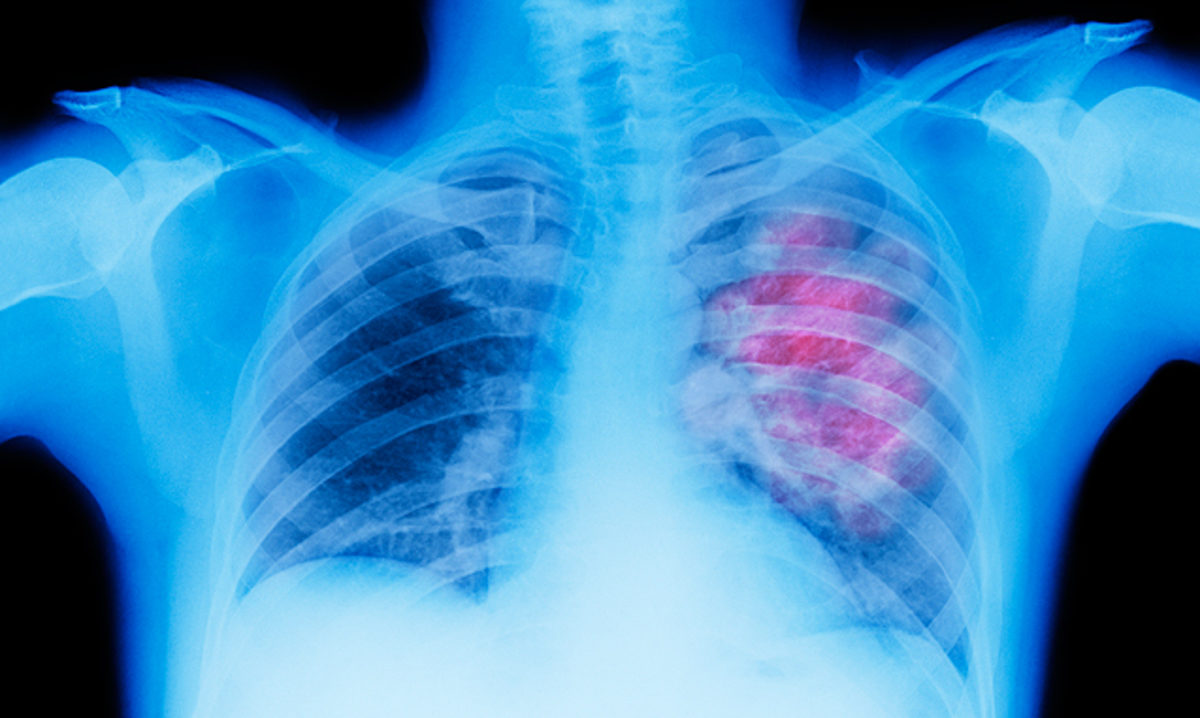

Καρκίνος του πνεύμονα: Δείτε όλα τα βήματα της θεραπείας

Ο καρκίνος του πνεύμονα αποτελεί την πρώτη αιτία θανάτου στους άντρες, ενώ στις γυναίκες τείνει να ξεπεράσει σε συχνότητα το καρκίνο του μαστού. Ταυτόχρονα, αποτελεί την πιο θανατηφόρα μορφή καρκίνου, με ποσοστά θνησιμότητας που αγγίζουν το 30%. Πως αντιμετωπίζεται; Ποια είναι η θεραπεία; Απαντήσεις στο επιστημονικό άρθρο που ακολουθεί.

Ο όρος «καρκίνος του πνεύμονα» ή «βρογχογενής καρκίνος» αναφέρεται στη διαδικασία ανάπτυξης και σχηματισμού κακοήθους όγκου στην περιοχή των πνευμόνων, και αποτελεί την πρώτη αιτία θανάτου στους άντρες, ενώ στις γυναίκες τείνει να ξεπεράσει σε συχνότητα το καρκίνο του μαστού.